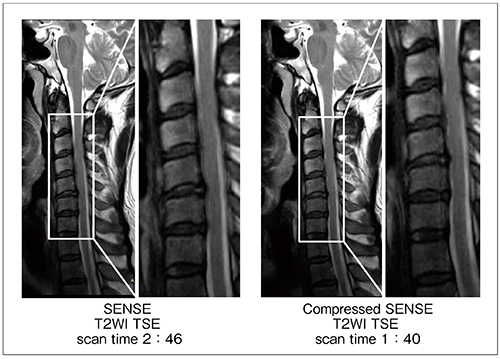

Compressed SENSEは,前述した技術により臨床応用へ高い期待が持てる。3D撮像のみならず,ルーチン検査のほとんどを占める2D撮像にも対応しているため,EPIやradial scanを除く,現状の撮像プロトコールにほぼ制限なく対応が可能である。また,50%以上の短縮率を図っても,画像劣化を最小限に抑えた画像が得られる(図3)。さらに,Optimized Variable-density Samplingは,効率的な撮像時間短縮を図る要素であるとともに,k-space中心部を密にランダムサンプリングすることから,モーションアーチファクトを減少させる特長も生まれる。図4は,2D-高速スピンエコーを用いたT2強調画像である。脊髄内に発生したモーション性のゴーストアーチファクトが,Compressed SENSEを併用した場合,減少していることが確認できる。

図3 Compressed SENSEのモーションアーチファクト低減効果